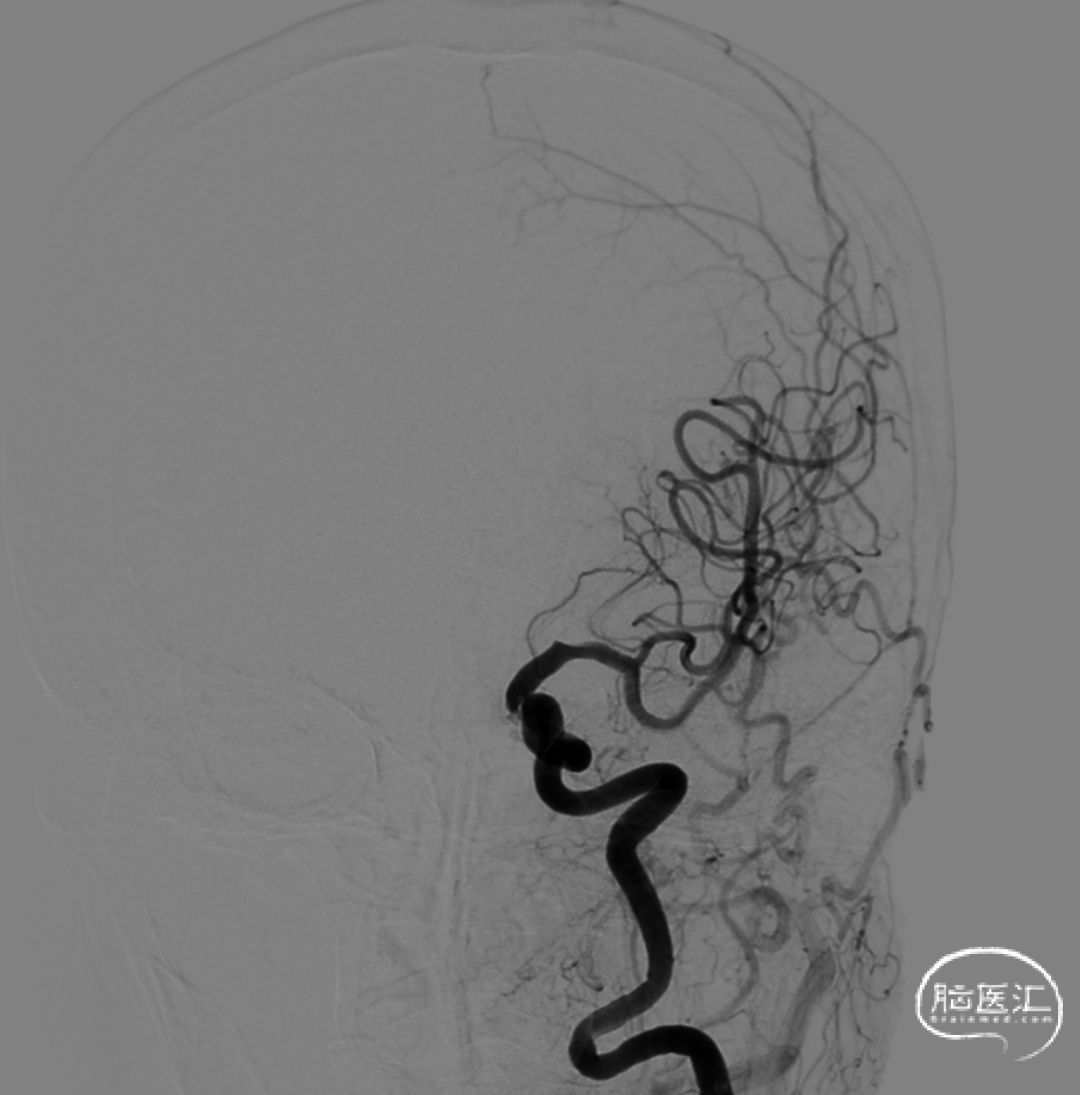

多角度造影明确左侧颈内动脉眼动脉段重度狭窄。

正位造影

侧位造影

将6F 115cm SKATHI远端通路导管撤至左侧颈内动脉C1起始,多角度造影显示左侧颈内动脉眼动脉段狭窄明显改善,颈内动脉通畅,颅内血流改善。